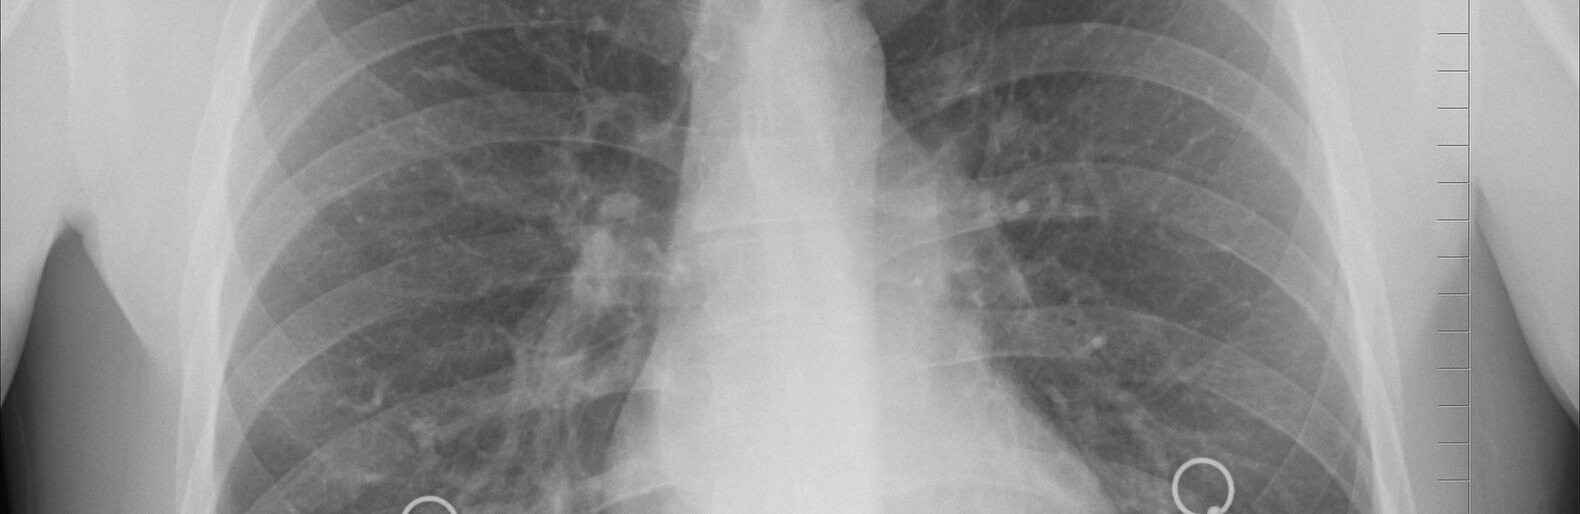

В Киеве у пациентов с пневмонией взяли образцы для проверки на коронавирус. 44.ua »